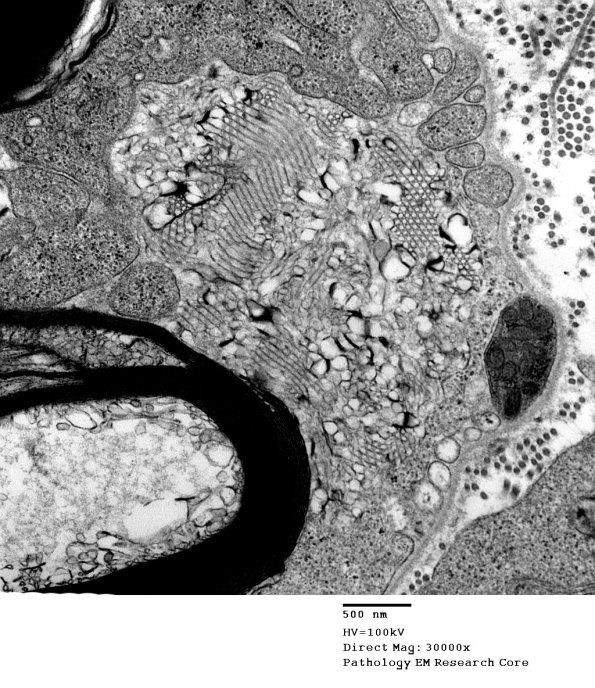

In this case the myelin is seen being directly converted into degraded vesicles.